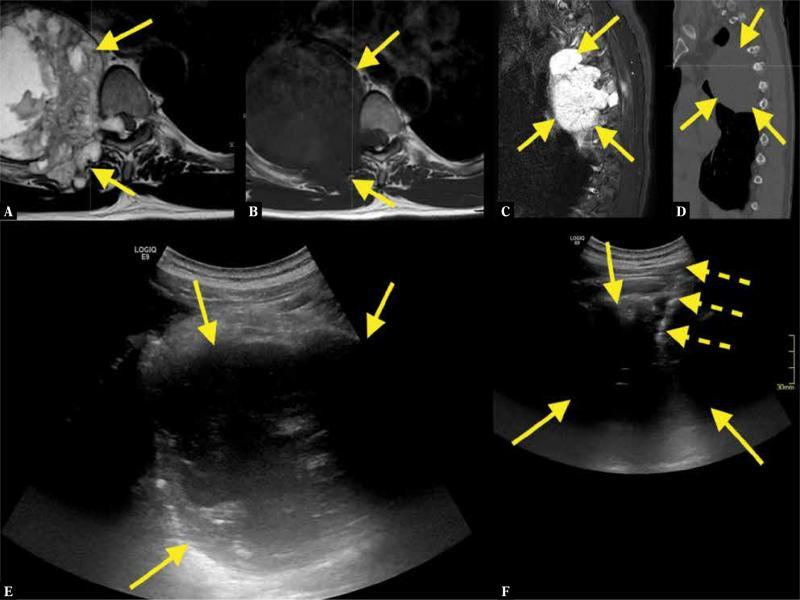

Fig. 2.

A 56-year-old patient presented to the emergency room because of pain in the thorax and clonus in the foot. An acute MRI of the whole spine revealed an about 10 cm long tumor ( A–C ; straight arrows – tumor). CT showed no calcifications ( D ). MRI and CT were unspecific, with a wide spectrum of differential diagnoses. US-CNB was performed ( E, F ; dashed arrows – biopsy needle). A histopathological diagnosis of chondrosarcoma was confirmed after excisional biopsy